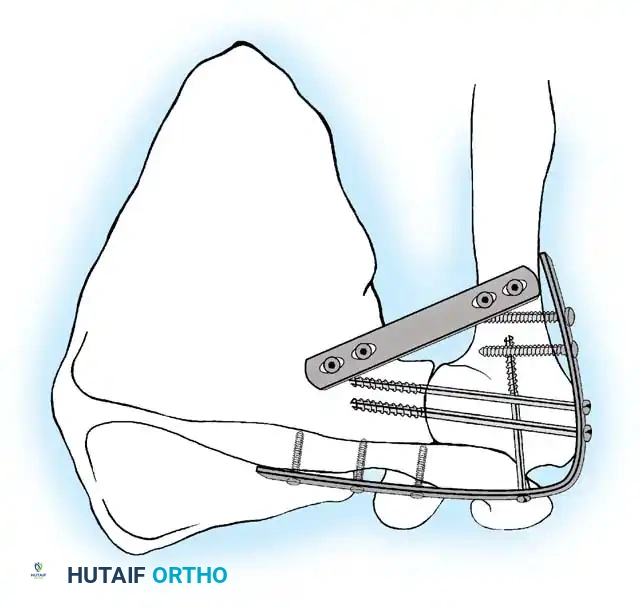

The paradigm shifted dramatically in the 1960s with the introduction of internal fixation. Moseley and May described techniques utilizing screw fixation, which minimized soft-tissue dissection and lowered infection rates but still carried a high nonunion rate without spica casting. In 1970, the AO group revolutionized the procedure by publishing a technique utilizing rigid plate and screw fixation, allowing patients to mobilize without a spica cast. Kostuik and Schatzker later introduced double-plating techniques (using a posterior buttress plate), achieving a 100% union rate in their series.

Miller et al. conducted a landmark biomechanical study evaluating various fixation constructs for shoulder arthrodesis. They demonstrated that double plating (utilizing 4.5 dynamic compression plates) provided the highest bending strength and torsional stiffness.

This was followed, in decreasing order of strength, by single plating, external fixation combined with screws, external fixation alone, and screws alone. Conversely, Rühmann et al. demonstrated in a cadaveric study that specific six-screw configurations could provide mechanical stability comparable to a 16-hole reconstruction plate. Today, the use of a malleable pelvic reconstruction plate is highly favored, as it allows for precise intraoperative contouring over the spine of the scapula and down the humeral shaft, minimizing hardware prominence while maintaining rigid compression.

5. Rigid Internal Fixation

The most robust biomechanical construct involves a heavy, malleable plate (such as a 10- to 14-hole 4.5mm pelvic reconstruction plate or a dynamic compression plate). The plate is meticulously contoured to lie flat along the spine of the scapula, bend over the acromion, and extend down the lateral shaft of the humerus.

Screws are placed sequentially:

1. Scapular Spine: Cortical screws are placed into the dense bone of the scapular spine.

2. Acromiohumeral Fixation: Screws are passed through the plate, across the acromion, and into the humeral head.

3. Glenohumeral Fixation: Long, fully threaded cortical or cancellous screws are directed through the plate, through the humeral head, and deep into the glenoid neck and vault. This is the most critical step for achieving compression across the primary fusion site.

4. Humeral Shaft: The distal portion of the plate is secured to the humeral diaphysis.

If additional stability is required, or if bone quality is poor, a second plate (double plating technique) can be applied posteriorly.

Radiographic confirmation of a contoured reconstruction plate achieving rigid acromiohumeral and glenohumeral compression.